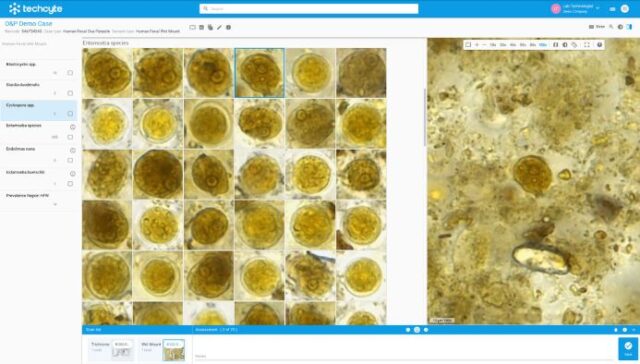

Built with pathologists to deliver an ultrafast cloud-based viewer, flexible worklist, integrated workflows, and state-of-the-art AI.

Techcyte Fusion: The unified anatomic and clinical pathology AI platform

What to expect from the Techcyte platform